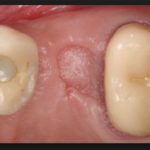

Можно ли Левомеколь накладывать пациенту на десну при пародонтозе, определяет врач в зависимости от стадии заболевания и ее протекания. Обычно мазь или гель входят в курс лечения. Особенно, если слизистая оболочка набухает, наблюдается кровотечение, зубы приобретают подвижность, а человек жалуется, что ему тяжело пережевывать пищу. Прилегающие ткани становятся рыхлыми и плохо держат зубы. Обычно стоматолог освобождает от гноя карман, наносит мазь и рекомендует пациенту Левомеколь, мазать десну в первые несколько дней после лечения или использовать тампоны с пропитками из нее.